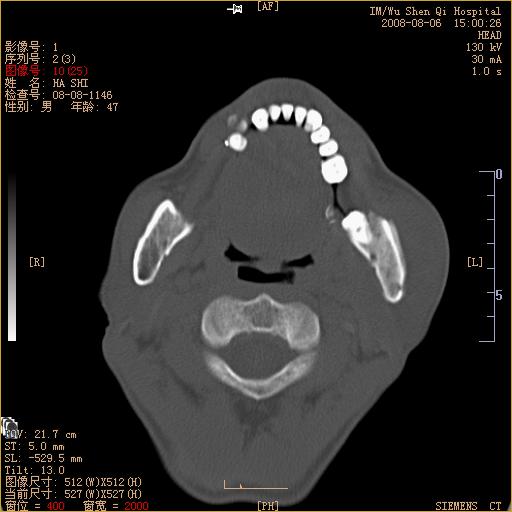

标题: CT15051:男 47岁 左下颌角部肿痛一周 [打印本页]

标题: CT15051:男 47岁 左下颌角部肿痛一周

骨质破坏,无硬化边,周围软组织肿胀,占位

左下颌骨感染性病变,牙源性可能。

左侧下颌智齿阻生。

考虑左下颌骨骨髓炎。